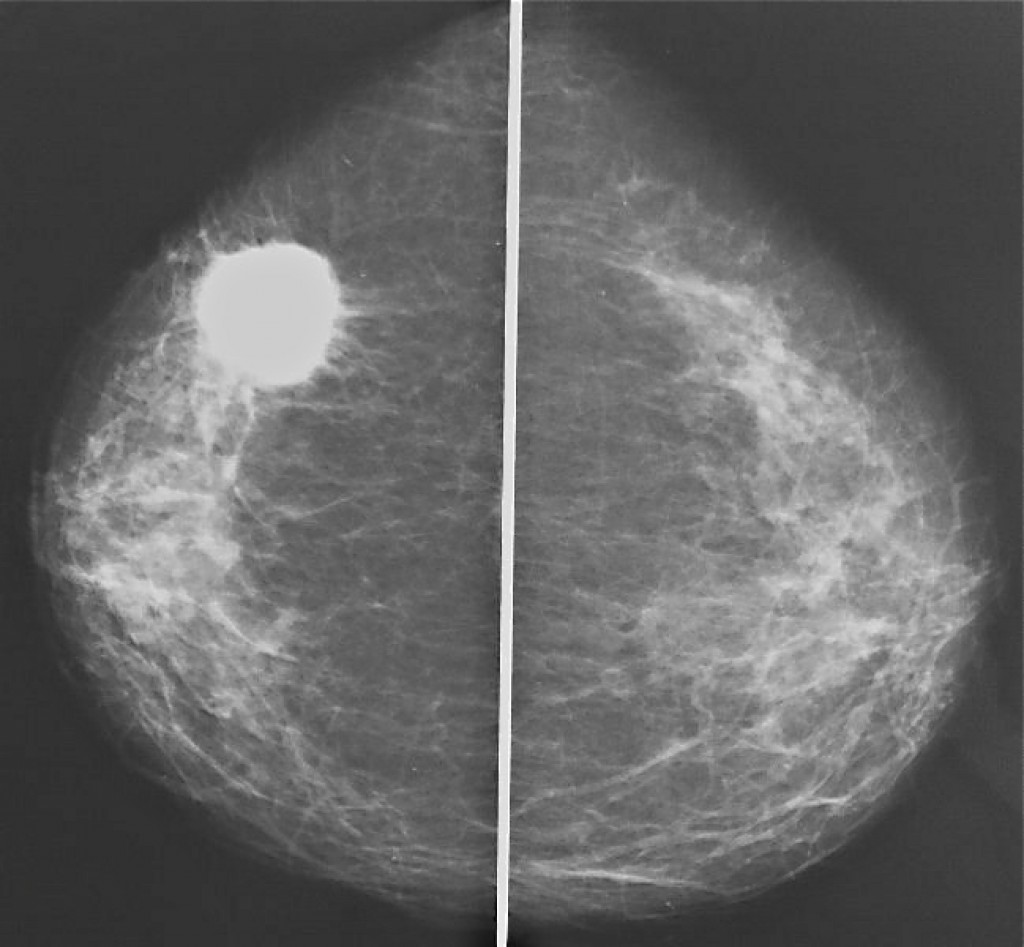

Аномалии молочной железы: медицинские примеры и визуализация

Раздел: Мудрость в деталях